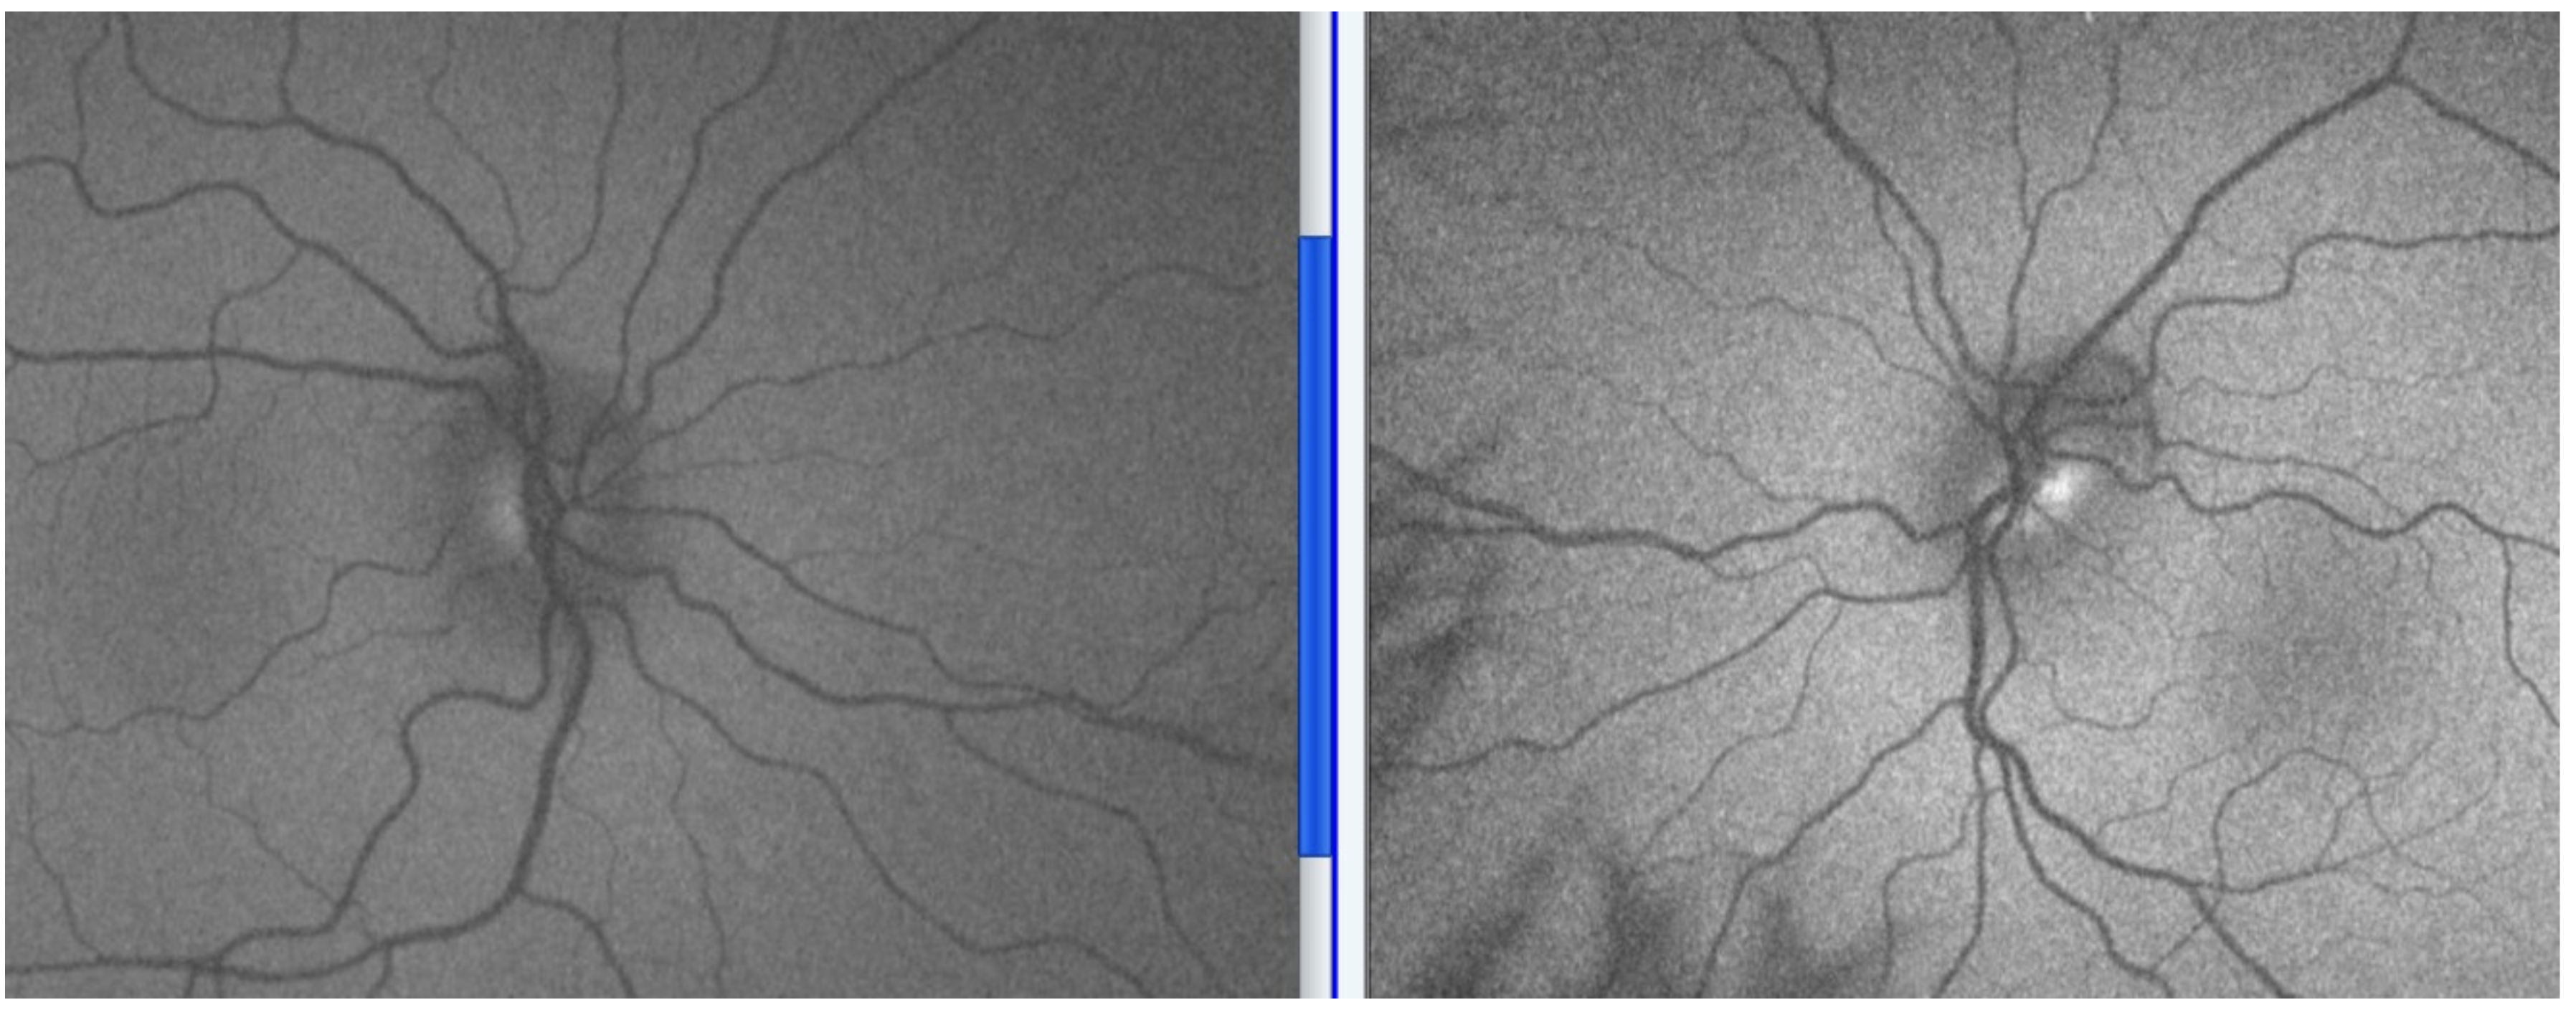

5.2. Signs

- Frisén, L. Swelling of the optic nerve head: A staging scheme. J. Neurol. Neurosurg. Psychiatry 1982, 45, 13–18. [Google Scholar] [CrossRef] [Green Version]